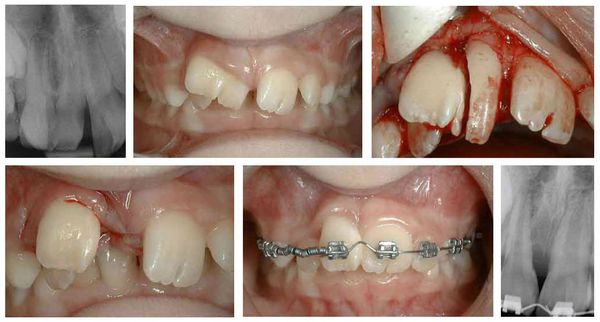

Makrodoncja (po lewej) i mikrodoncja (po prawej)

Podwojenie i zlanie zębów (fuzja lub germinacja) najczęściej prowadzą do problemów estetycznych — zęby wydają się zbyt duże, asymetryczne lub mają nieregularny kształt. Od typowego stłoczenia zębów (stłoczenie zębowe) można je odróżnić jedynie na podstawie badania rentgenowskiego, które pokazuje, czy zęby mają wspólne korzenie lub komory miazgi.

Rozdwojony ząb (po lewej) i zrośnięte zęby (po prawej): wygląd zewnętrzny i zdjęcie rentgenowskie